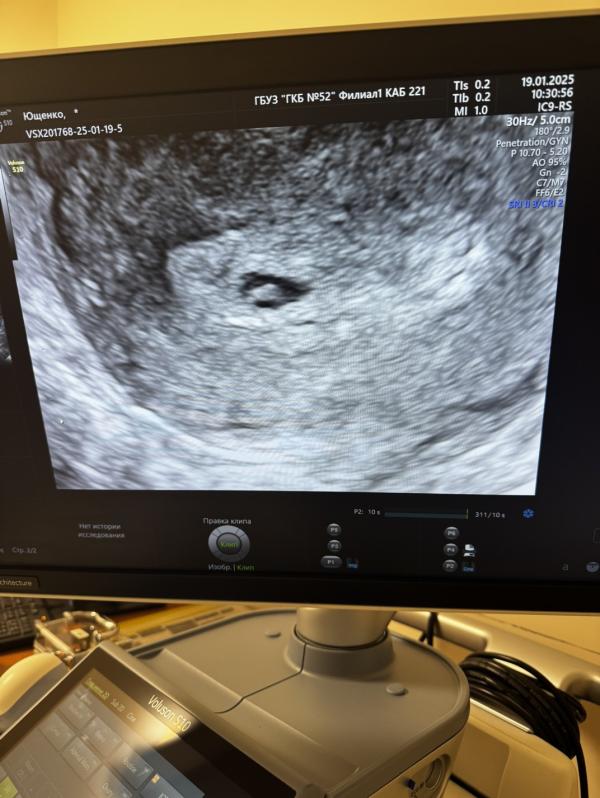

Вот и закончилась моя вторая беременность выкидышем на 6 недели 🥲🥲🥲

Спасибо, что была возможность послушать твое сердцебиение первый и последний раз ❤️